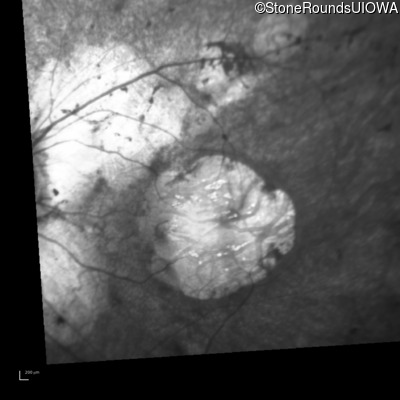

Infrared Fundus Photograph - Left - 20/100 -1

Exemplar